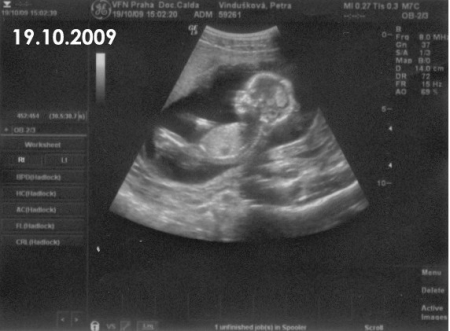

15. týden těhotenství pokračuje rychlý růst tělíčka plodu do délky. Na konci 4. měsíce tvoří hlavička asi třetinu celkové délky plodu. Mozek pokračuje ve svém vývoji. Na jeho povrchu se již vytvořila tenká vrstvička šedé hmoty.

Na povrchu hlavičky začíná být patrná část porostlá vlasy. Na okrajích očních víček se objevují jemné řasy. Oční víčka jsou stále srostlá.

Boltec ouška má už v podstatě definitivní tvar.

Celé tělíčko je pokryté velmi tenkou pokožkou. Jsou v ní již založeny všechny obvyklé vrstvy. Objevují se první buňky, které obsahují pigment. Jejich množení patří k faktorům, které v budoucnu ovlivní zbarvení kůže. Celý povrch těla je pokryt velmi jemnými kožními chloupky (lanugo).

V 15. týdnu těhotenství plod měří od temene k zadečku 9 - 10 cm, váží asi 40 – 50 g.